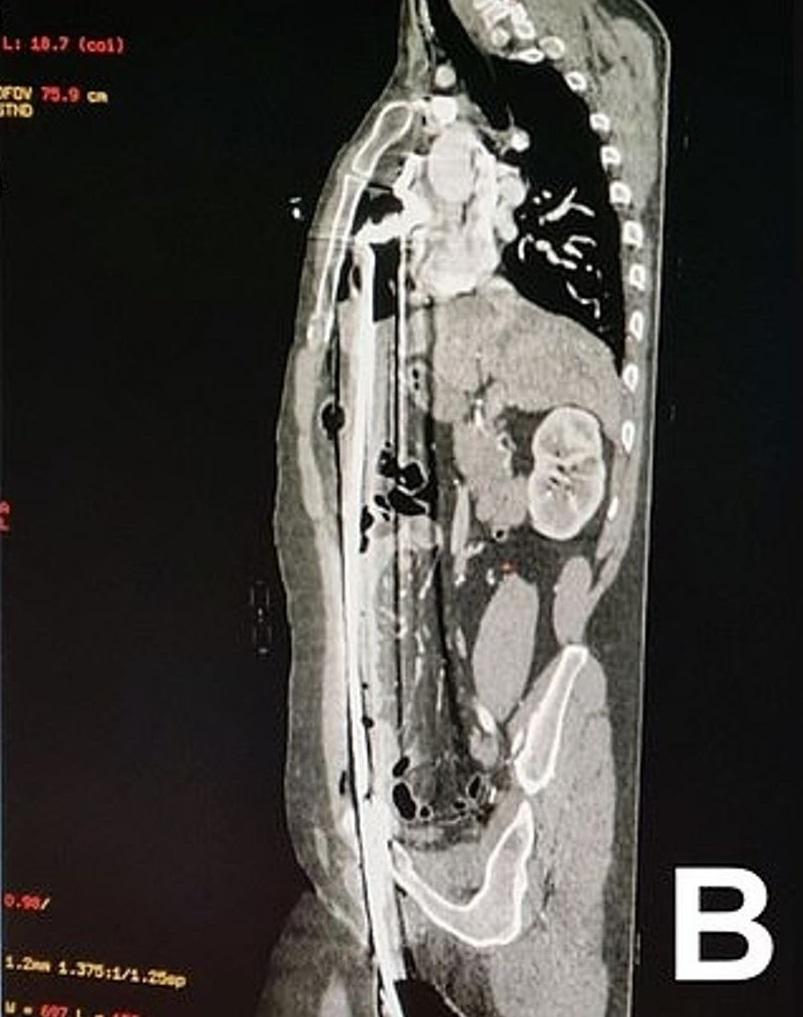

掃描圖像顯示,長鋼條從男子下體插進體內,直到肺部下方。(互聯網)

醫生指,該名男子被長約91厘米的鋼條,從下體插入並貫穿上半身,插到肺部與橫隔膜附近位置,肝臟被穿刺,所幸避過心臟。男子被送院急救,醫生初步檢查發現,其心率、血壓和血氧狀況,出奇地都正常。

醫生當時判斷,男子有生命危險,於是立即動手術。剖腹後,醫生將部分胸骨切開,從體內取出鋼條後,再縫合腹部。